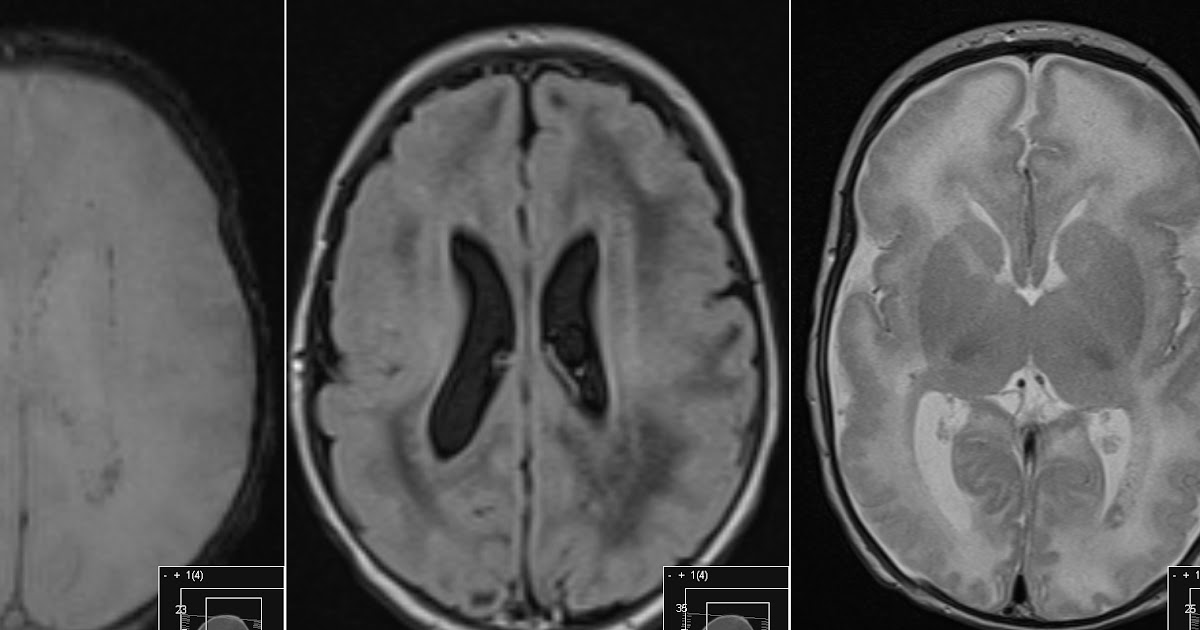

Neuroradiology On the Net Congenital Cytomegalovirus infection

Radiology MRI Congenital Cytomegalovirus Infection

Pediatric Cytomegalovirus Encephalitis Pediatric Radiology Reference Article Pediatric

Image Congenital Cytomegalovirus Infection MSD Manual Professional Edition